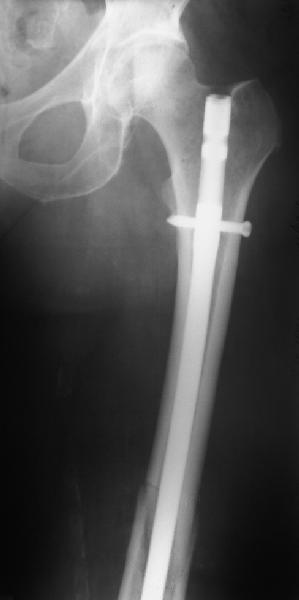

Хотя закрытый остеосинтез блокированным гвоздем выглядит технически проще, особенно при диафизарных переломах. Не говоря о биомеханических преимуществах внутрикостного имплантата, еще меньшей инвазивности, возможности динамизации при проблемах со сращением... Стоимость гвоздей и пластин сопоставимая, на рынке есть масса отечественных предложений.

В приложении - недавний перипротезный перелом.

Методичка по закрытому интрамедулярному остеосинтезу при дистальных переломах бедра тут.